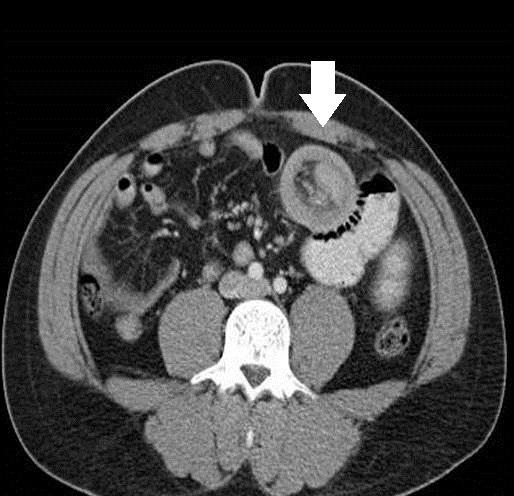

Adult Intussusception Secondary to Inflammatory Fibroid Polyp.

https://cdn.ncbi.nlm.nih.gov/pmc/blobs/9711/4530921/7f0122b38d01/wjem-16-581-g001.jpg